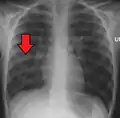

![]() | |

| Chest X-ray of a pneumonia caused by influenza and Haemophilus influenzae, with patchy consolidations, mainly in the right upper lobe (arrow) | |

A chest radiograph is frequently used in diagnosis.[23] In people with mild disease, imaging is needed only in those with potential complications, those not having improved with treatment, or those in which the cause is uncertain.[23][67] If a person is sufficiently sick to require hospitalization, a chest radiograph is recommended.[67] Findings do not always match the severity of disease and do not reliably separate between bacterial and viral infection.[23]

X-ray presentations of pneumonia may be classified as lobar pneumonia, bronchopneumonia, lobular pneumonia, and interstitial pneumonia.[73] Bacterial, community-acquired pneumonia classically show lung consolidation of one lung segmental lobe, which is known as lobar pneumonia.[41] However, findings may vary, and other patterns are common in other types of pneumonia.[41] Aspiration pneumonia may present with bilateral opacities primarily in the bases of the lungs and on the right side.[41] Radiographs of viral pneumonia may appear normal, appear hyper-inflated, have bilateral patchy areas, or present similar to bacterial pneumonia with lobar consolidation.[41] Radiologic findings may not be present in the early stages of the disease, especially in the presence of dehydration, or may be difficult to interpret in the obese or those with a history of lung disease.[24] Complications such as pleural effusion may also be found on chest radiographs. Laterolateral chest radiographs can increase the diagnostic accuracy of lung consolidation and pleural effusion.[40]